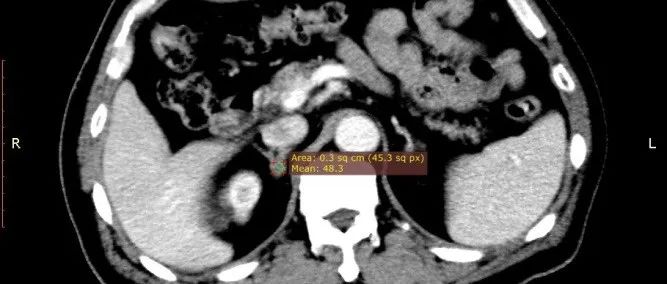

老年男性,右肾上腺肿物1月,请诊断!

医学影像  yxyx-app  医学影像APP,打造伴随医生快速成长的影像学习社区。与影像园(Xctmr.com)一起提供最全面的影像案例库、基础(解剖、病理、影像诊断)知识、影像技术及考题等,为医生提供最佳的医学影像参考。【所属科室】普外科【基本资料】患者,男,72岁【主诉】发现右肾上腺肿物1月【现病史】发现右侧肾上腺肿物1月,近3个月无明显诱因出现血压升高,既往高血压病史10余年。...

医学影像APP 2022-06-29